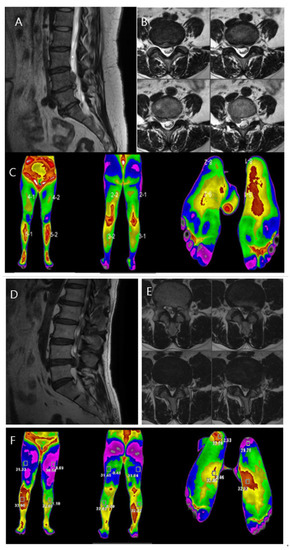

3.4. Case Discussion